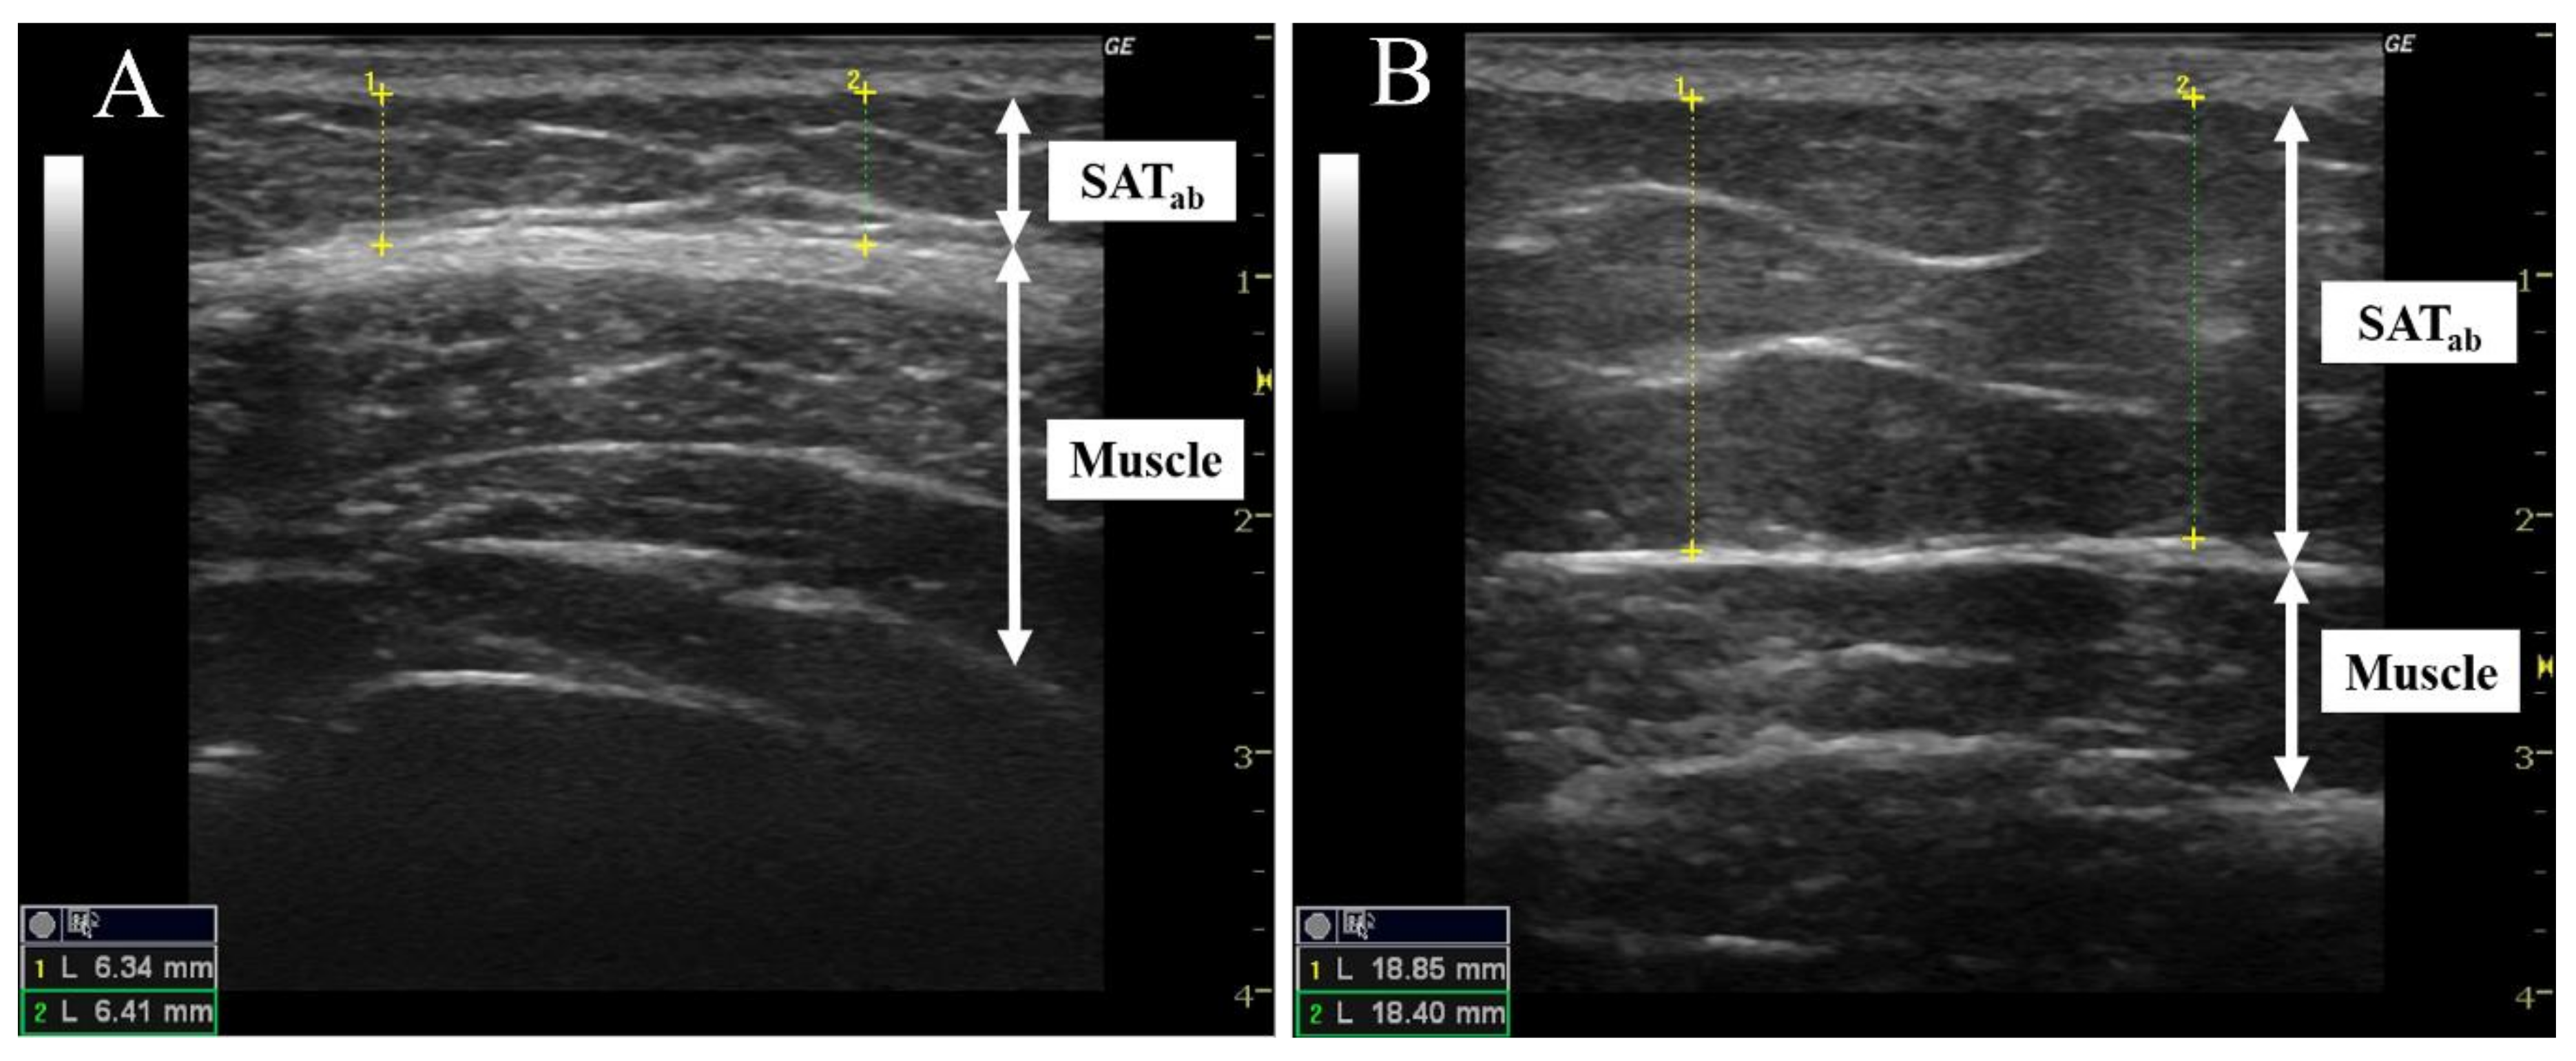

3.2. The Thickness Threshold of the Subcutaneous Adipose Tissue in the Abdomen (SATab)